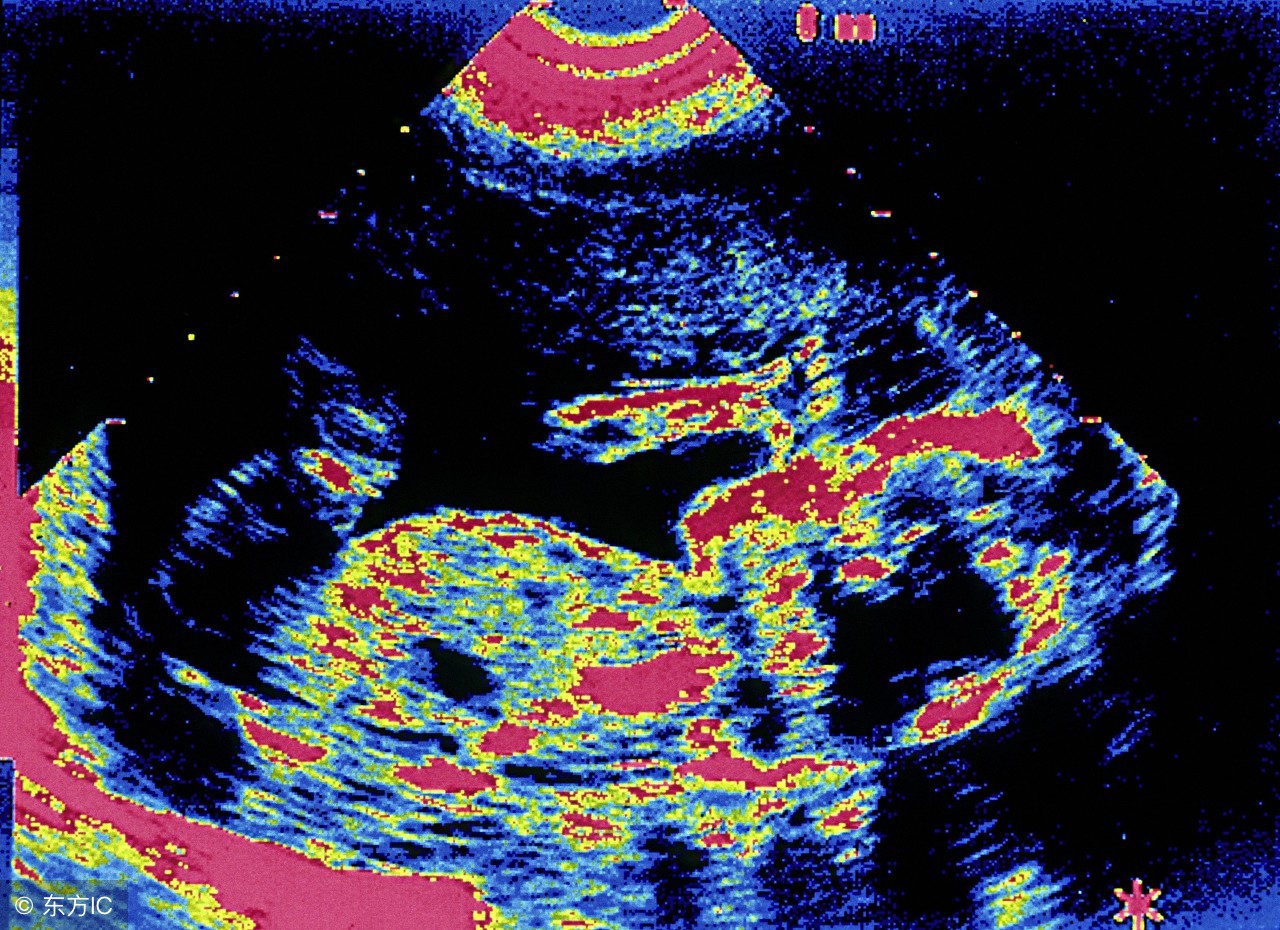

孕妇生殖器宫异常,比如子宫畸形存在双子宫、子宫发育不良等,这都会引发自然小产的发生。情绪不稳定,怀孕期间,孕妇情绪受到刺激,过度的悲哀、愤怒等激烈的情绪变化,都会引发子宫收缩发生小产。